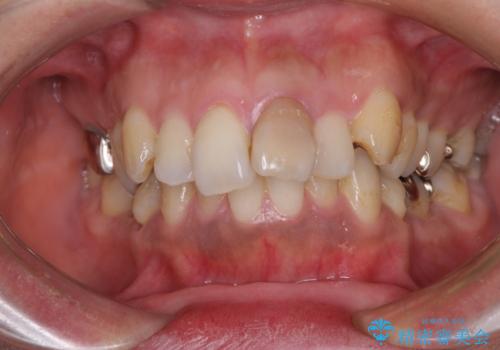

前歯の出っ歯と口の閉じにくさが気になる 目立たないワイヤー装置での抜歯矯正

担当医 藤巻太一朗